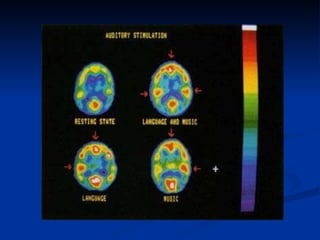

Efeito Mozart Em 1989, o neurobiólogo americano Gordon Shaw, da Universidade de Irvine, realizou um estudo provando que a música de Mozart era capaz de aumentar a capacidade de cognição espaço-temporal. Frances Raucher realizou estudos com ratos demonstrando que a exposição de ratos à música de Mozart melhorava a performance de ratos em um labirinto.  Mais recentemente, Shaw e colegas usaram aparelhos de ressonância magnética para mapear as áreas do cérebro que são ativadas pela música – ressonância magnética funcional. Percebeu-se então que, além do córtex auditivo, onde o cérebro processa os sons, a música também ativa partes associadas com a emoção e, com Mozart, todo o cérebro é ativado.

Efeito Mozart Em1989, o neurobiólogo americano Gordon Shaw, da Universidade de Irvine, realizou um estudo provando que a música de Mozart era capaz de aumentar a capacidade de cognição espaço-temporal. Frances Raucher realizou estudos com ratos demonstrando que a exposição de ratos à música de Mozart melhorava a performance de ratos em um labirinto. Mais recentemente, Shaw e colegas usaram aparelhos de ressonância magnética para mapear as áreas do cérebro que são ativadas pela música – ressonância magnética funcional. Percebeu-se então que, além do córtex auditivo, onde o cérebro processa os sons, a música também ativa partes associadas com a emoção e, com Mozart, todo o cérebro é ativado.